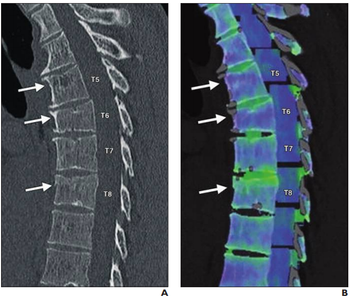

Spectral CT provides greater detail about the extent of ground-glass opacities than conventional CT scans.